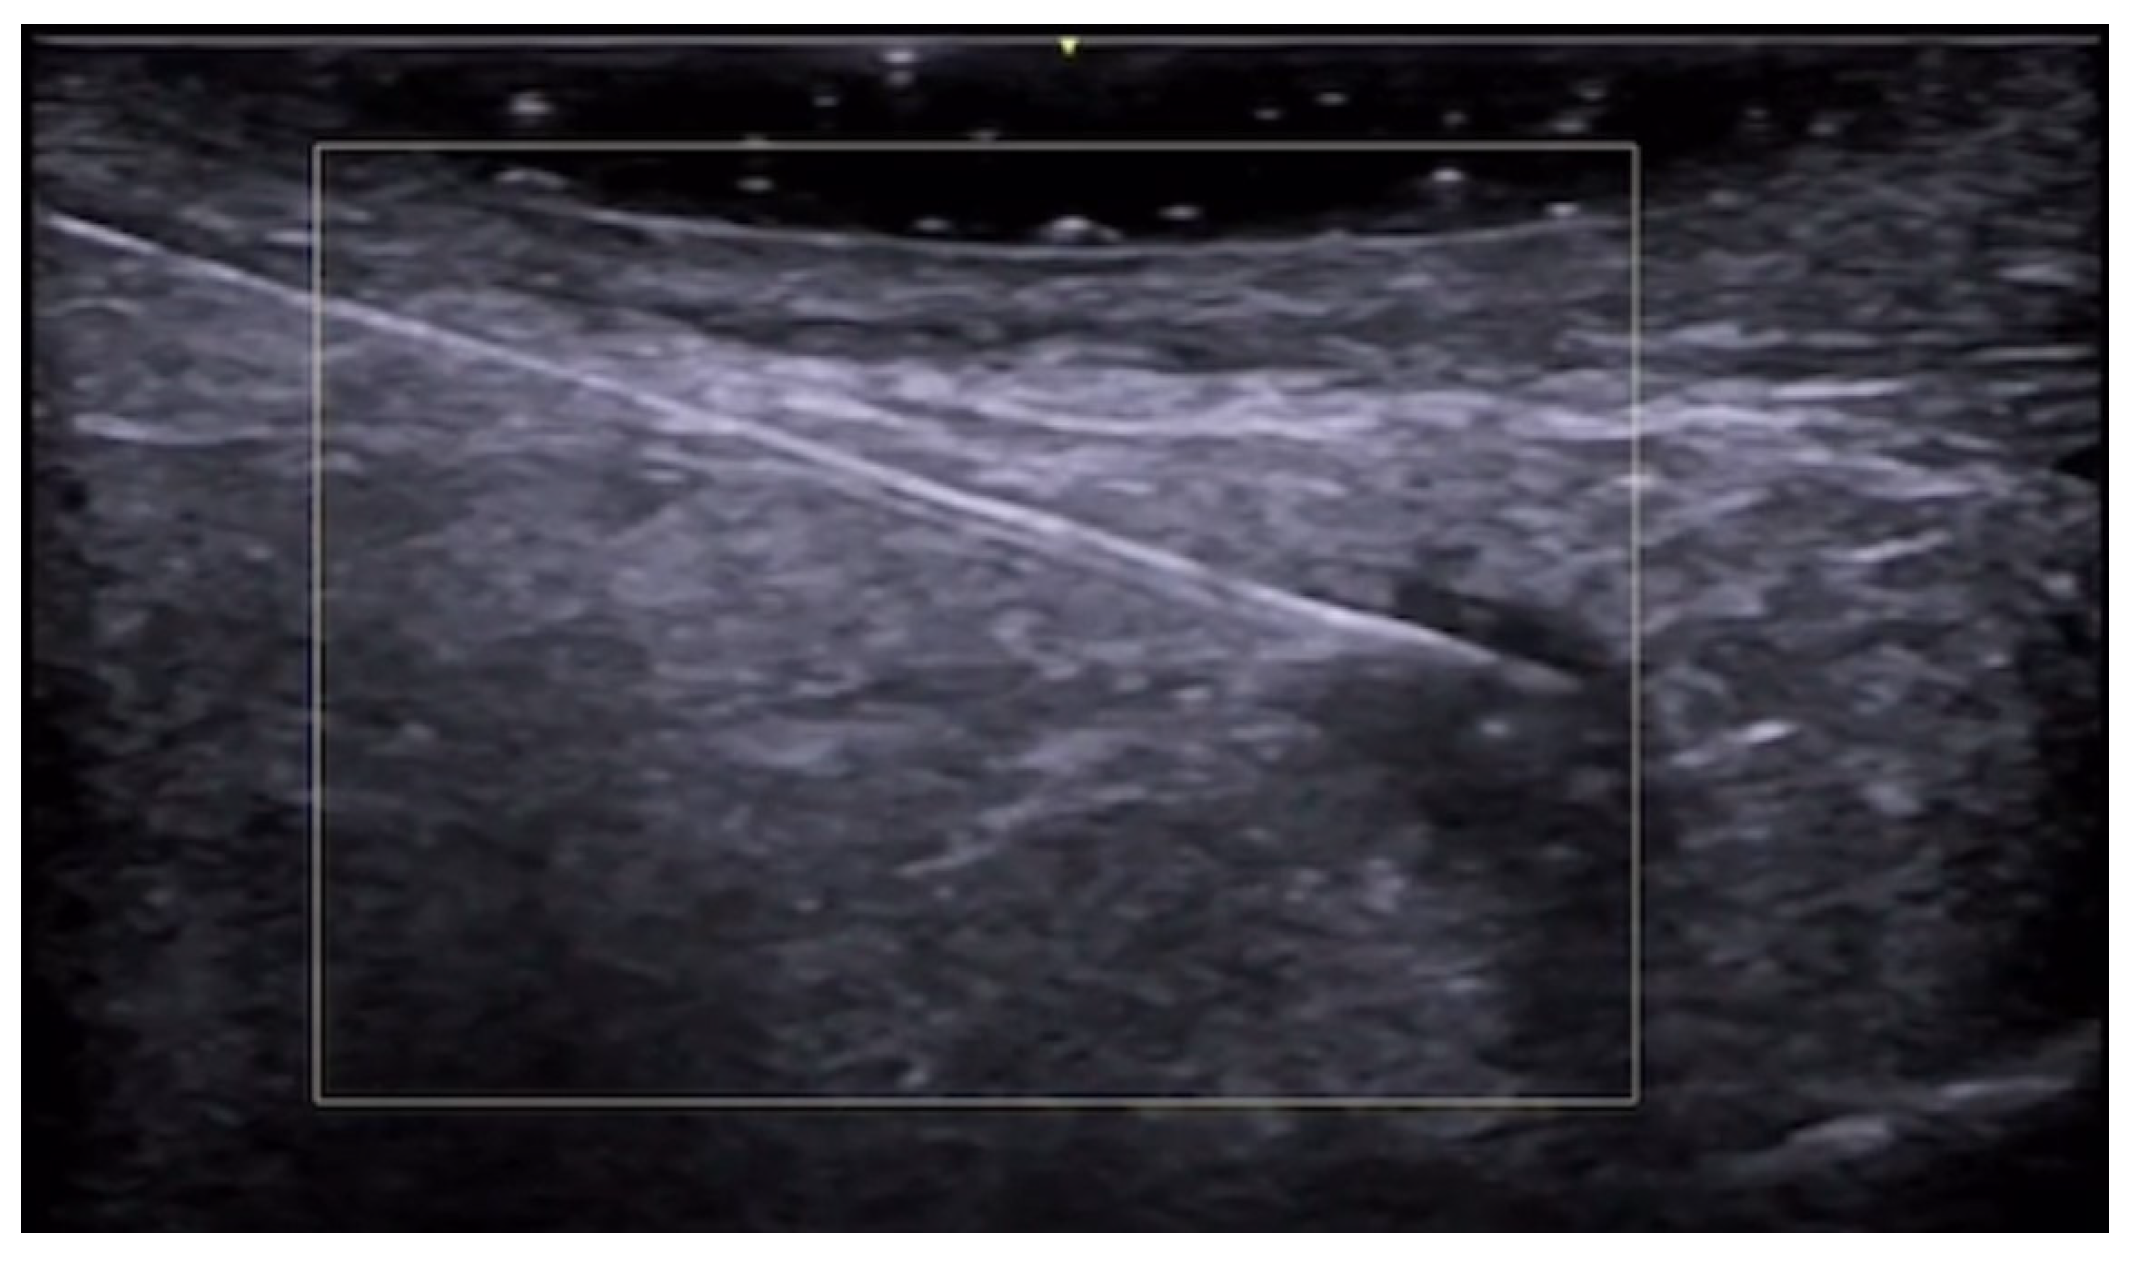

- Velthuis, P.J.; Jansen, O.; Schelke, L.W.; Moon, H.J.; Kadouch, J.; Ascher, B.; Cotofana, S. A Guide to Doppler Ultrasound Analysis of the Face in Cosmetic Medicine. Part 1: Standard Positions. Aesthetic Surg. J. 2021, 41, NP1621–NP1632. [Google Scholar] [CrossRef]

- Vasconcelos-Berg, R.; Izidoro, J.F.; Wenz, F.; Müller, A.; Navarini, A.A.; Sigrist, R.M.S. Doppler Ultrasound-Guided Filler Injections: Useful Tips to Integrate Ultrasound in Daily Practice. Aesthetic Surg. J. 2023, 43, 773–783. [Google Scholar] [CrossRef]